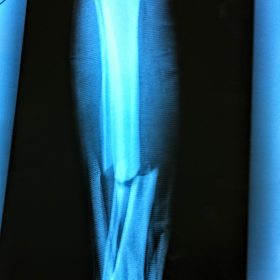

Κατάγματα Μηριαίου ή Κνήμης

Τα κατάγματα της Διάφυσης των οστών της κνήμης και του Μηριαίου οστού στη σύγχρονη ΟΡΘΡΟΠΑΙΔΙΚΗ αντιμετωπίζονται με ΕΝΔΟΜΥΕΛΙΚΗ ΗΛΩΣΗ.